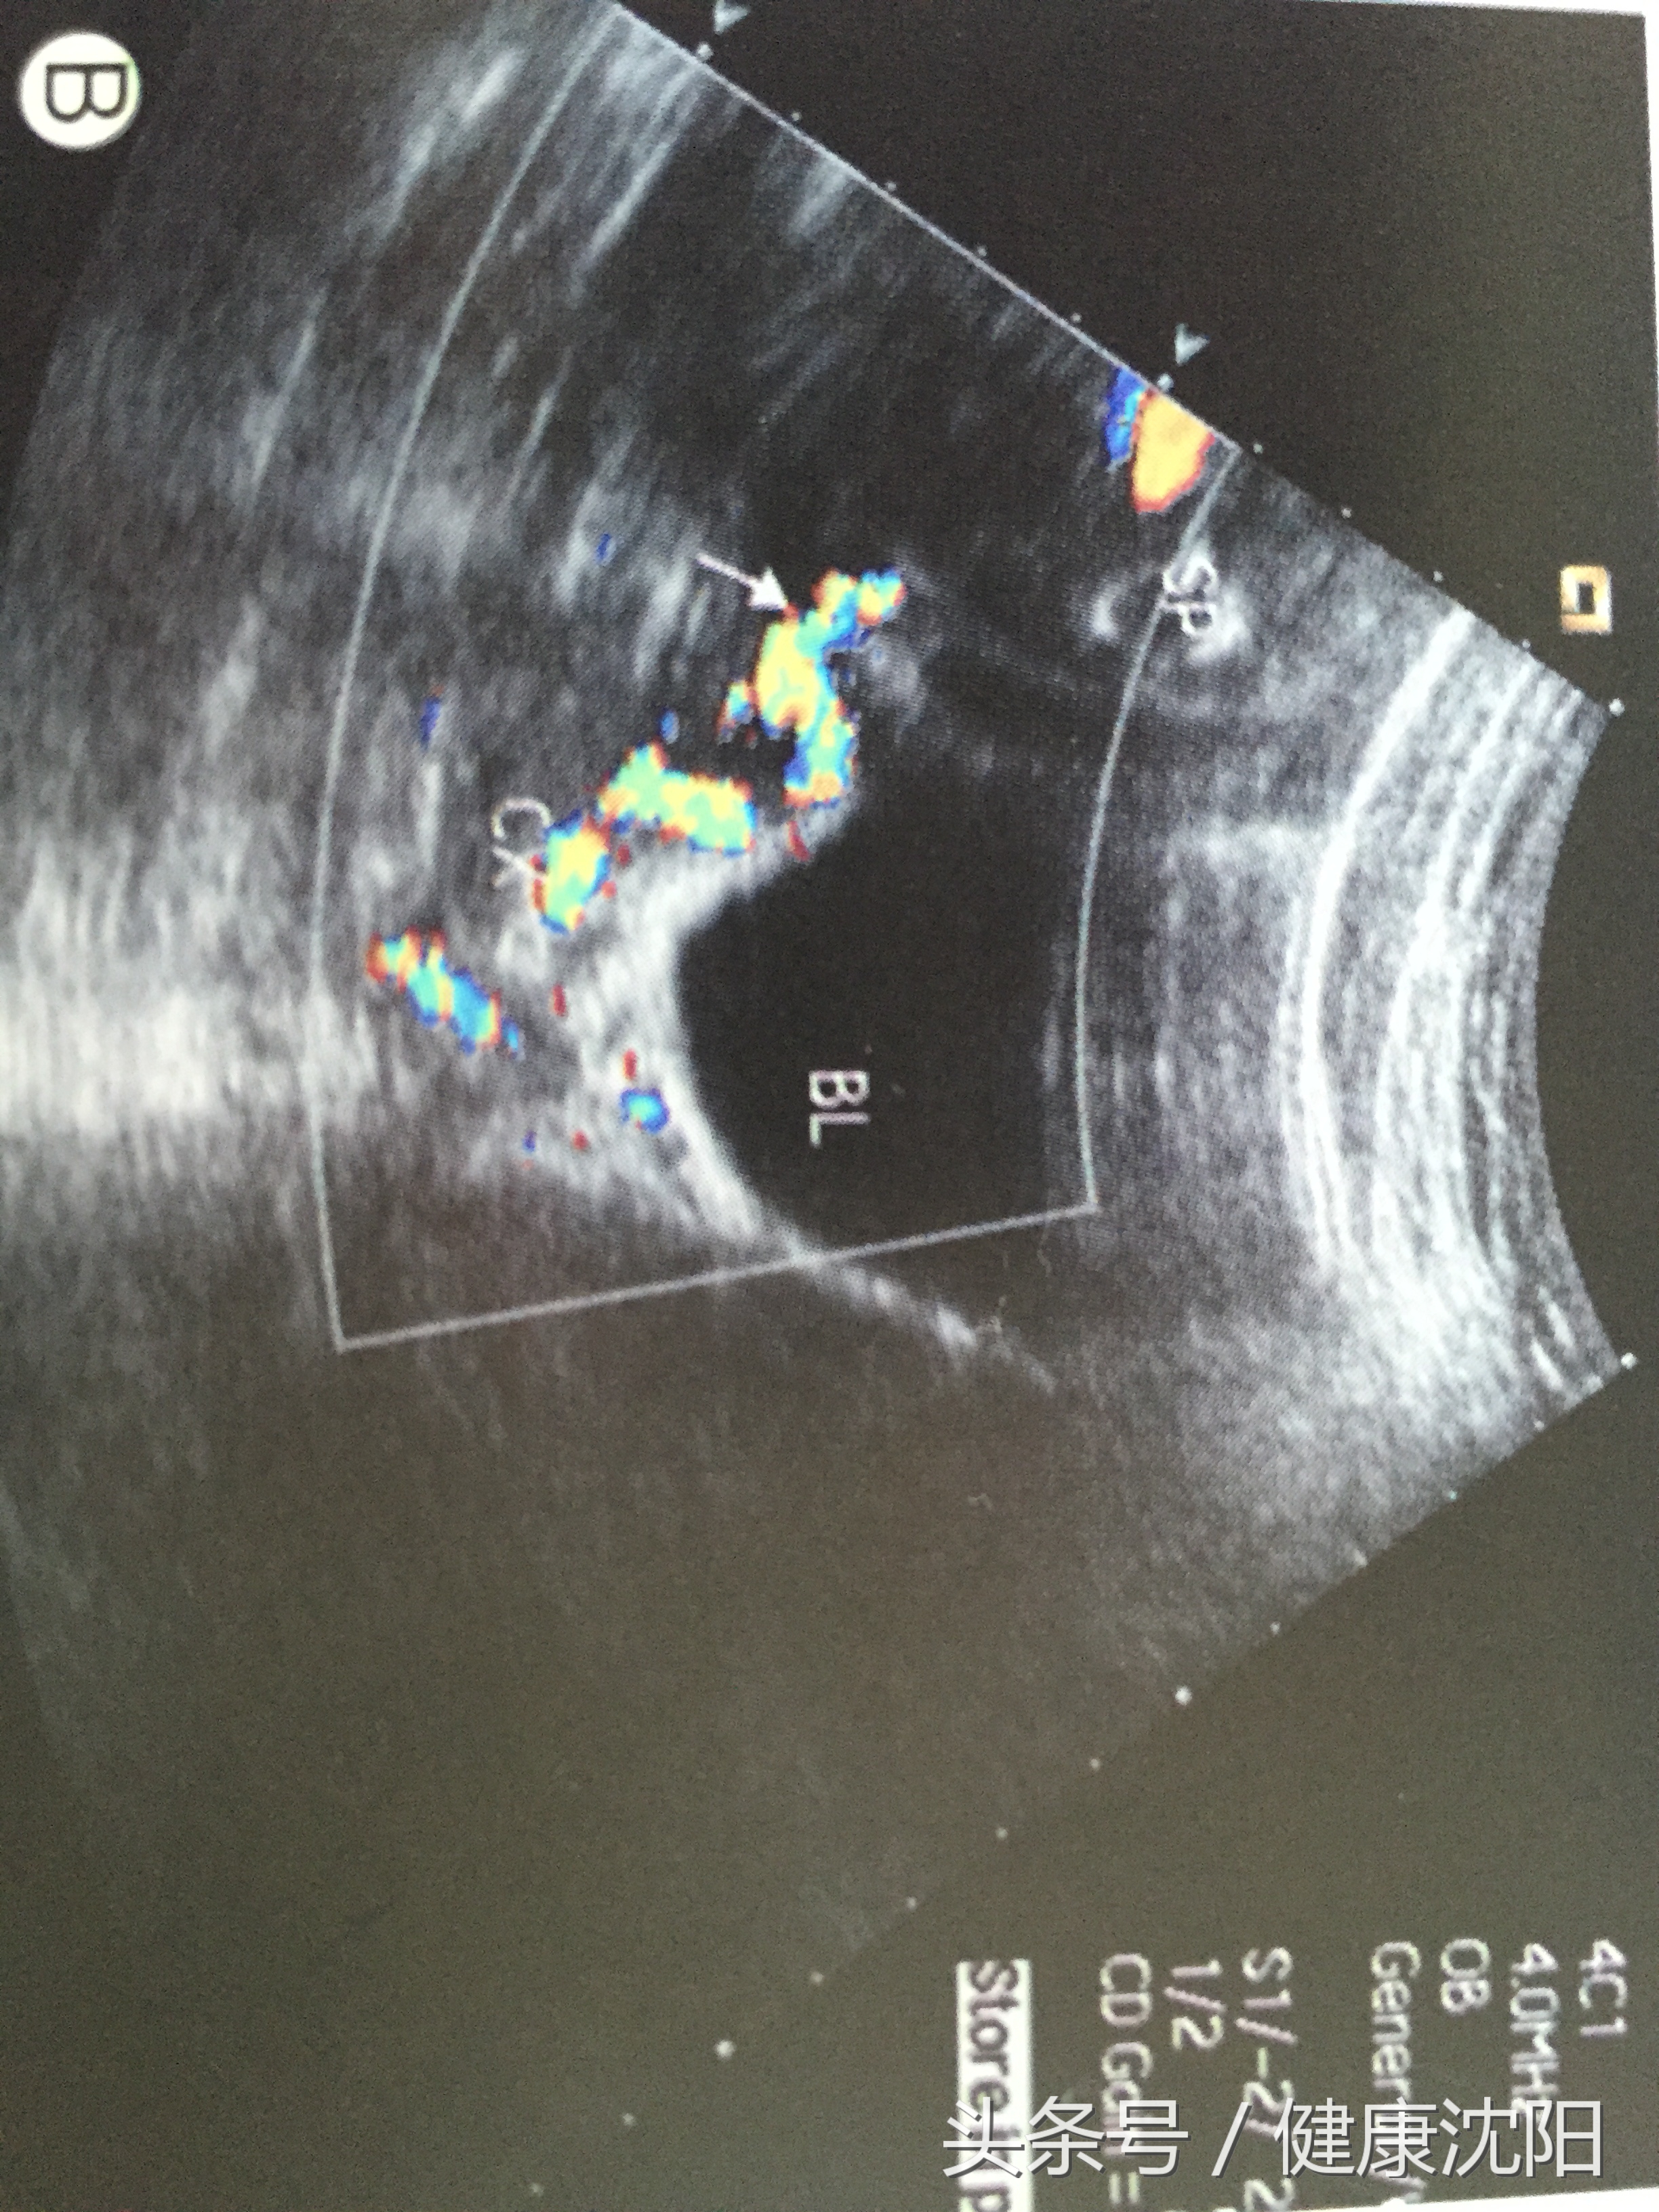

二维超声显示位于宫颈之上的血管横切面呈多个圆形无回声,纵切面呈条形或曲线形无回声。

帆状胎盘脐带入口,超声显示脐带的胎盘入口处的脐血管不立即进入胎盘组织,其脐带血管可以相互分开,呈扇形,位于胎膜内。如果超声显示帆状胎盘脐带入口位于胎盘下段,则应警惕有无血管前置,注意这些扇形分布的胎膜血管是否位于宫颈内口上方。

频谱多普勒或彩色多普勒对诊断血管前置极其有用,当疑宫颈内口有胎膜脐带血管时,彩色多普勒超声不仅可直接显示呈扇形分布的帆状脐带入口的胎膜血管或连接主副胎盘之间的胎膜血管,而且可获得典型的胎儿脐动脉频谱,故彩色多普勒超声可明确诊断血管前置。

经阴道超声扫差对显示覆盖在宫颈内口的血管较经腹部扫查更敏感。